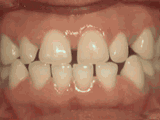

前牙移位,因为有牙齿缺失,导致相邻牙齿开始没有秩序的前突,经过矫正后是变成这样的~

前牙移位,因为有牙齿缺失,导致相邻牙齿开始没有秩序的左右移动,经过矫正后是变成这样的~

前牙移位,因为有牙齿缺失,导致相邻牙齿开始没有秩序的乱移动,经过矫正后是变成这样的~